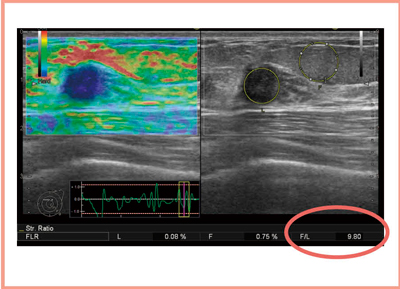

組織間のひずみの比(Strain Ratio)を定量評価する方法として,乳腺領域では,脂肪(Fat)と腫瘤(Lesion)のひずみの比を取るFLRがある。FLRは,腫瘤のひずみの平均で脂肪のひずみの平均を割り算して計算するが,簡単に言えば「脂肪に比べて腫瘤は何倍硬いのか」を数値で表すものである(図1)。

日立アロカメディカル社の“Real-time Tissue Elastography(RTE) ”では,FLRは図1のように,Bモード画像上で腫瘤と脂肪のそれぞれのROIを設定すると,そのひずみの平均を出して,比を計算する。その数字が画面の右下に表示されるが,図1の症例の場合は9.80となり,脂肪に比べて腫瘤は9.8倍硬いという数値的な評価が得られる。

図1 FLR(Fat Lesion Raito)